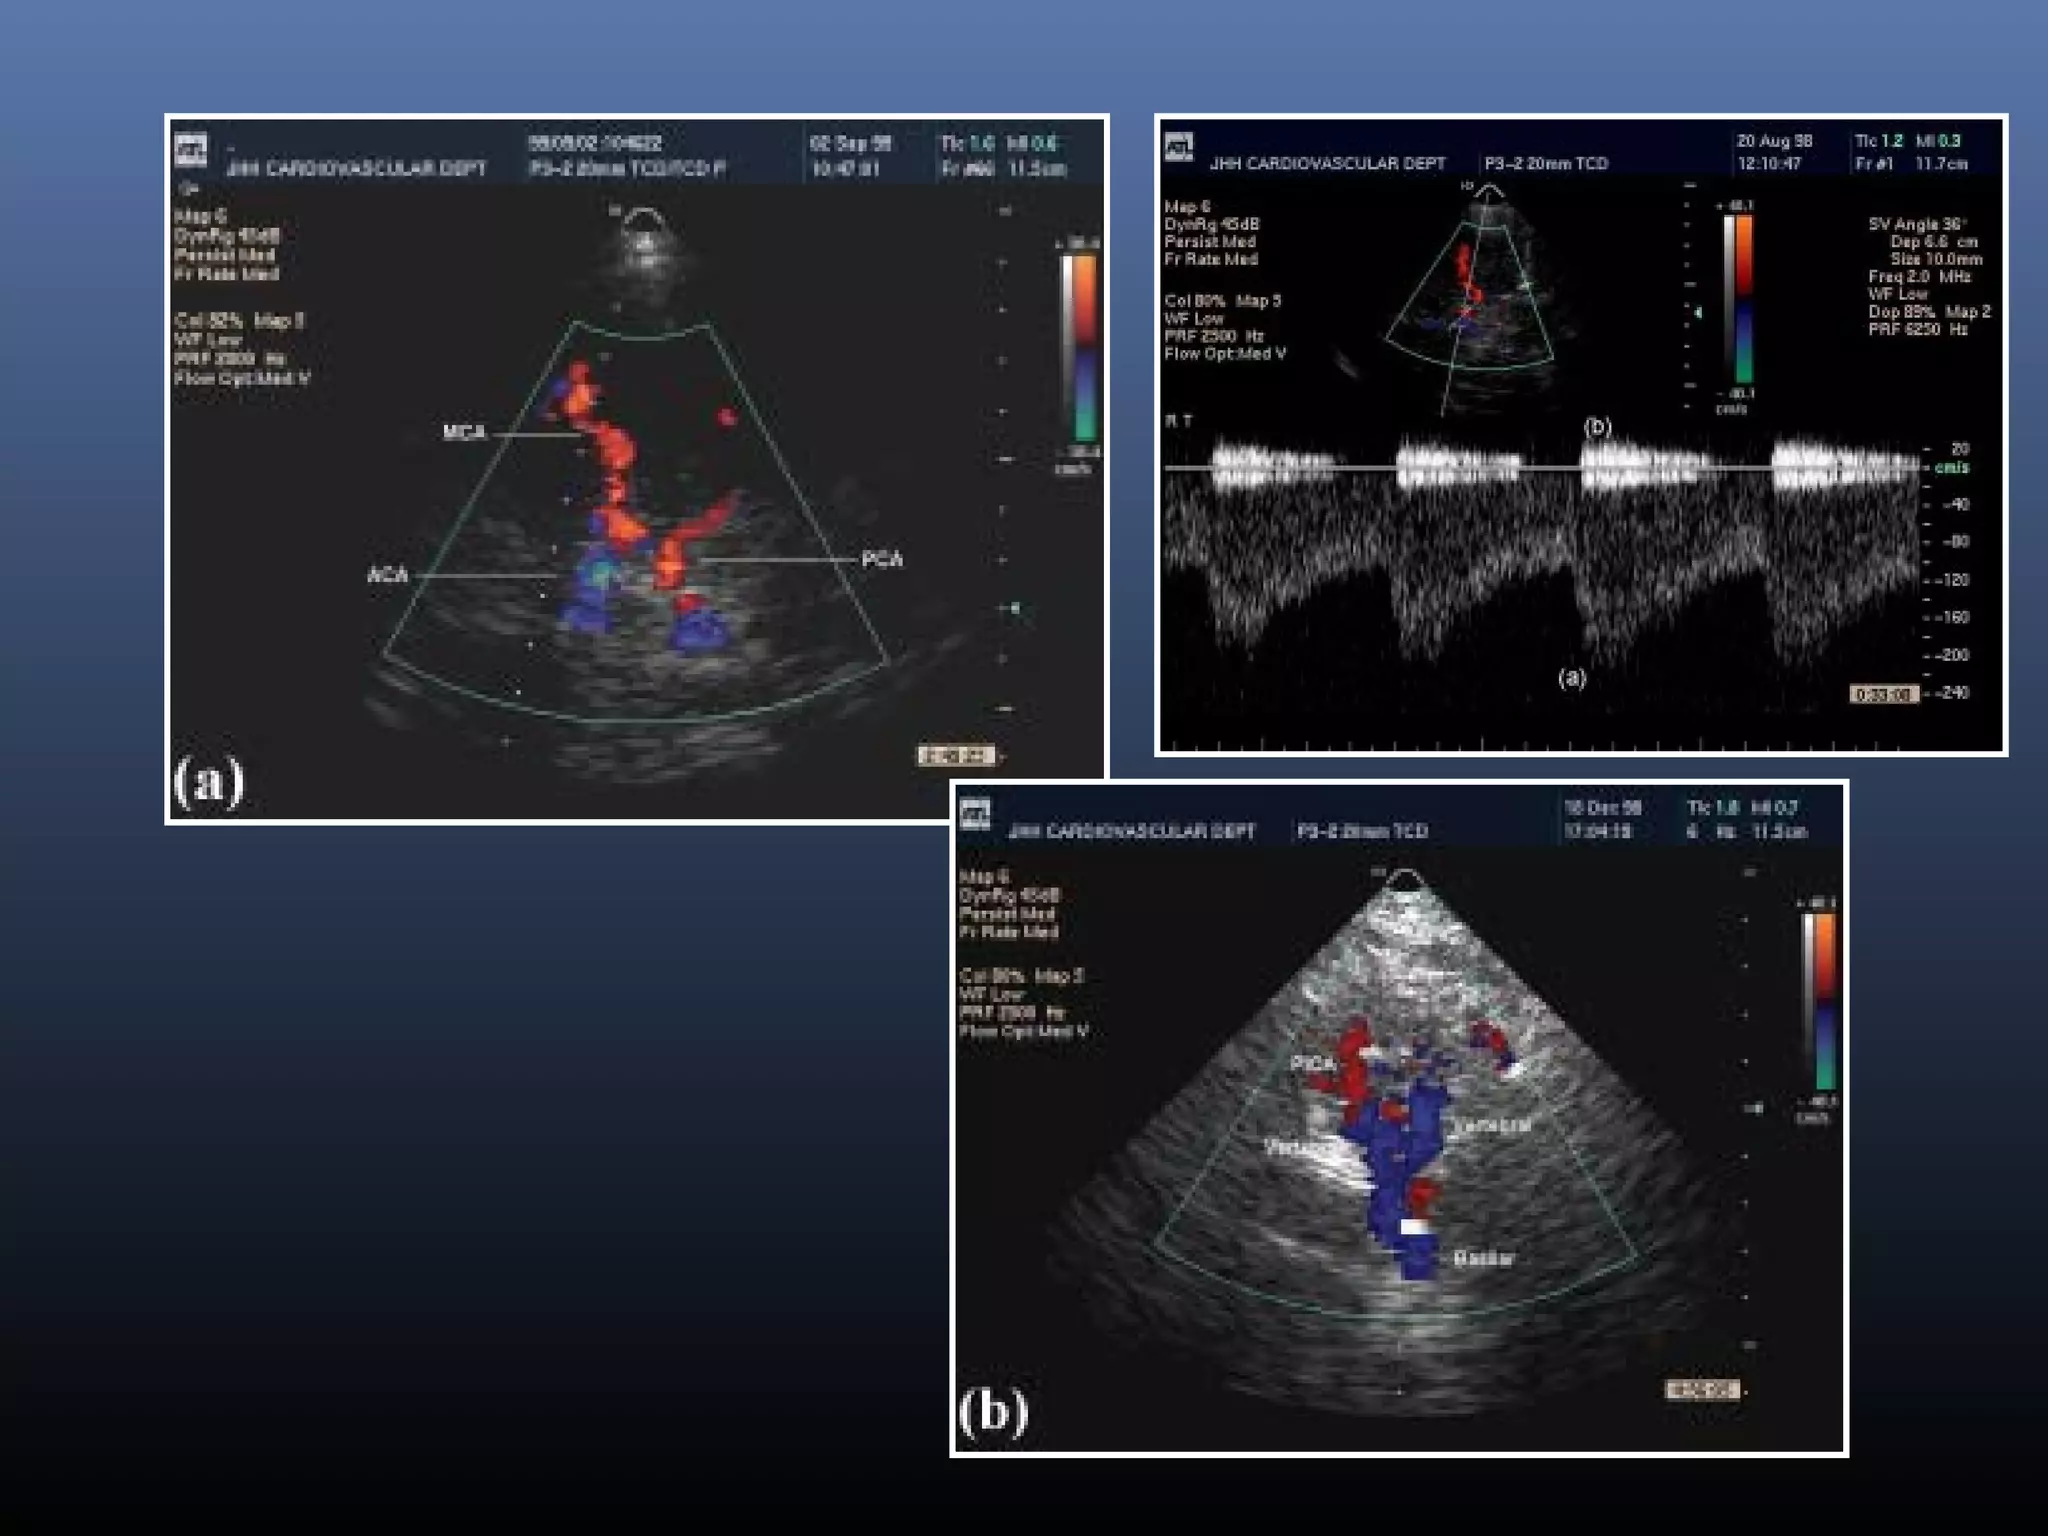

Transcranial doppler USG

 TCD

2 MHz ,pulsed range gated device

Low band width, large less defined volume

 TCCS

B mode+Frequency based color coding

1.8to 3.6 MHz

Rapid reliable vessel identification

Can also image parenchyma

Transcranial doppler USG-

M1 and M2 of MCA

C1 of ICA

A1 of ACA

P1 and P2 of PCA

Vertebral arteries

Basilar artery

Temporal approach Suboccipital approach

 Indications

Intracranial stenosis or occlusion

Secondary effects of extra cranial occlusion

Monitoring of vessel recanalization in stroke

Detection of microemboli

 Accuracy and pitfalls

sensitive and specific if stenosis > 50%

Accurate in detecting M1 lesions

Poor window in 10% - 20% of patients